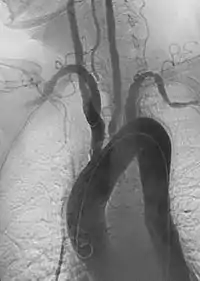

![]() Imagen angiográfica oblicua anterior izquierda de la arteritis de Takayasu que muestra áreas de estenosis en múltiples grandes vasos | ||